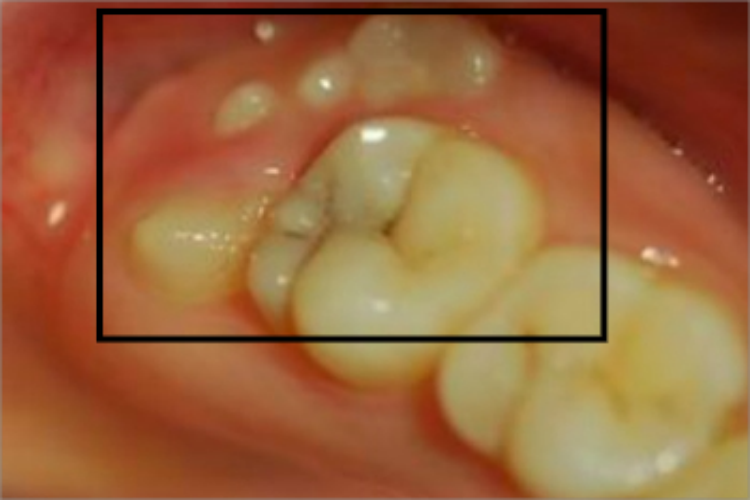

阻生牙可表现为牙床上有零星几个白点冒出,质地坚硬,是未完全萌出的阻生牙齿部分,进食时食物残渣易留存于白点之间,会导致白点龋损。